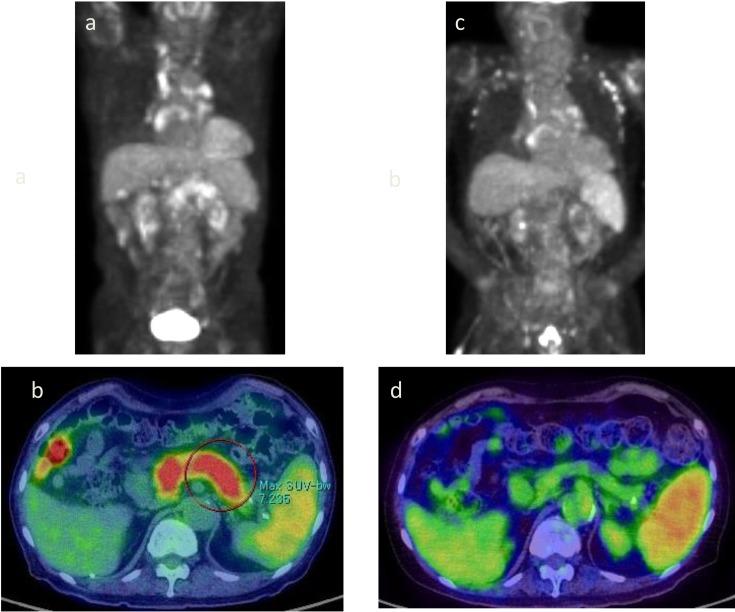

A 79-year-old man with elevated blood glucose was started on insulin therapy. IgG4 was as high as 1,830 mg/dL, and F-fluorodeoxyglucose-positron emission tomography/computed tomography (FDG-PET/CT) confirmed diffuse pancreatic enlargement and accumulation of FDG. Based on the above, autoimmune pancreatitis (AIP) was diagnosed, but steroid treatment was not performed. IgG4 later declined, and FDG accumulation in the pancreas disappeared on FDG-PET/CT at the age of 83 years. AIP was thought to have gradually remitted spontaneously over time. FDG-PET/CT is useful for evaluating AIP activity.

一名血糖升高的79岁男性开始接受胰岛素治疗。IgG4高达1830mg/dL,氟脱氧葡萄糖正电子发射断层扫描/计算机断层扫描(FDG-PET/CT)证实胰腺弥漫性肿大及FDG摄取。基于上述情况,诊断为自身免疫性胰腺炎(AIP),但未进行类固醇治疗。后来IgG4下降,83岁时胰腺的FDG摄取在FDG-PET/CT上消失。AIP被认为随时间推移逐渐自发缓解。FDG-PET/CT对评估AIP的活动情况很有用。